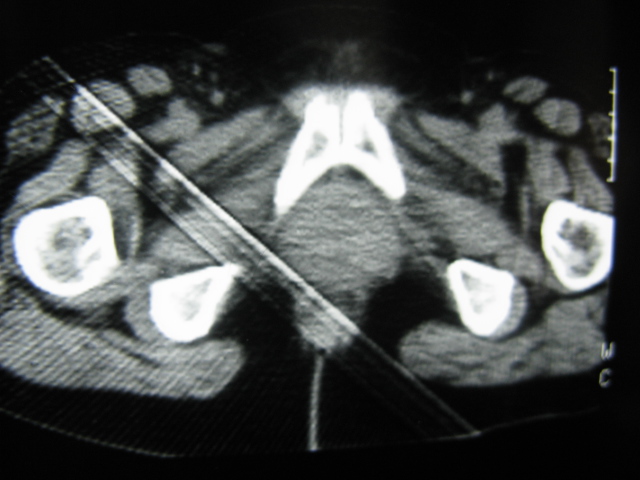

患者,女,64岁,2002年诊断为宫颈癌,当时只做过放,化疗。现在诊断:(1)宫颈癌。(2)直肠癌。请同道们讨论,探讨。另外肠壁为啥密度这么高,ct值约112hu。患者没有做过增强和造影。

高密度的不是肠管影,是肠管内的粪便影

患者直肠病变,排便不畅,粪便硬结造成,更高密度如钡灌肠者都可出现

难定宫径癌,直肠癌